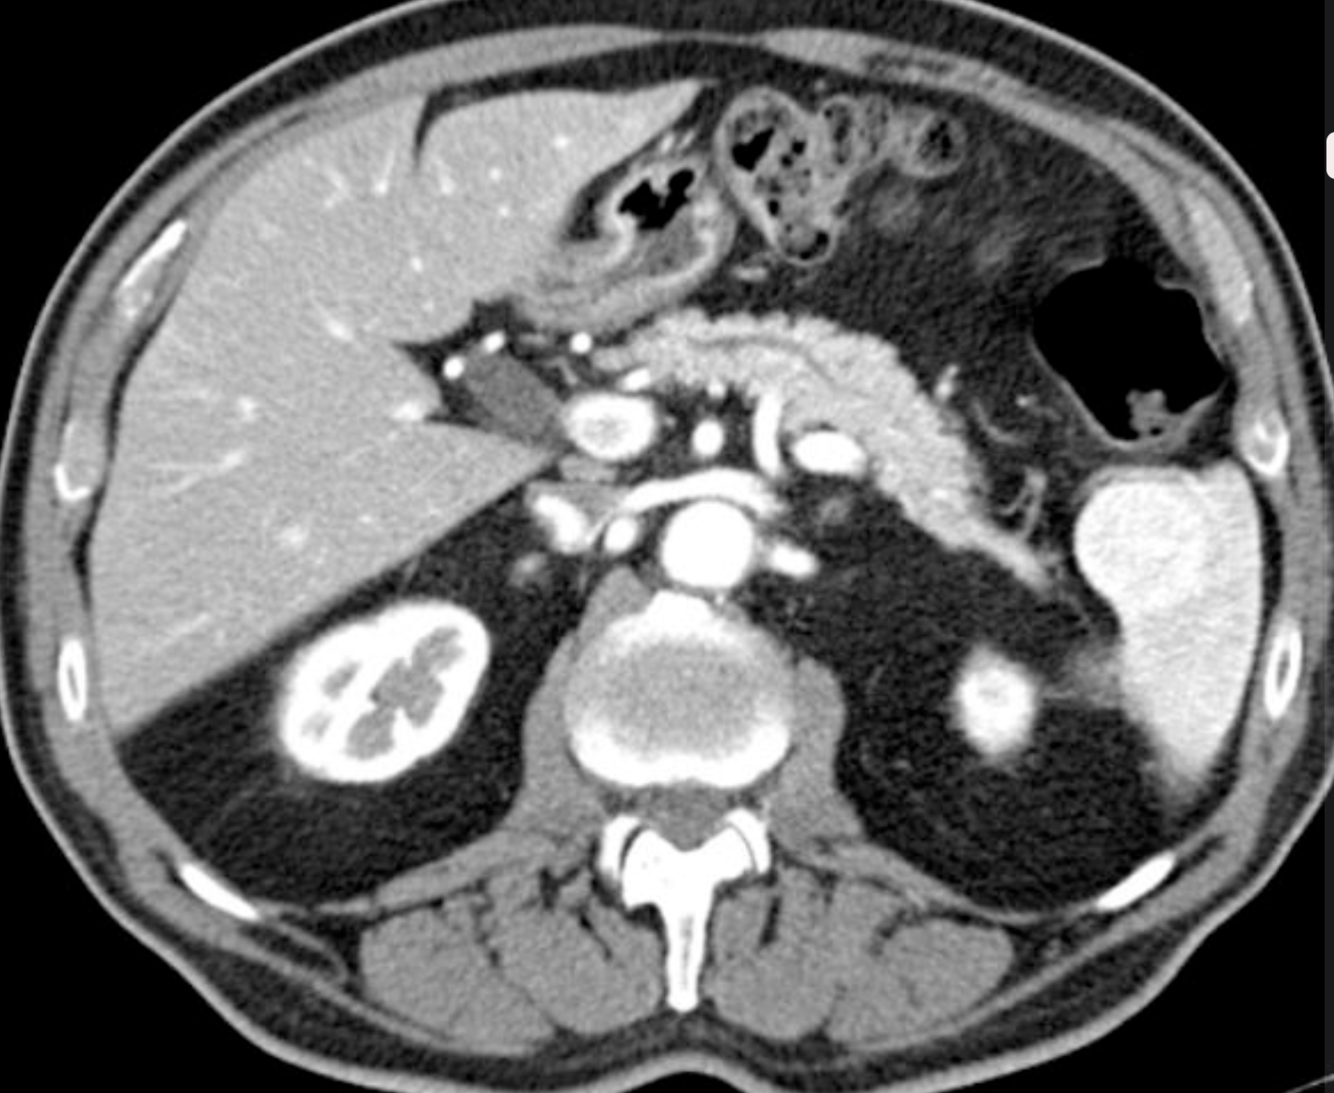

There is an intraparenchymal haematoma/laceration measuring > 5 cm which extends to the splenic hilum. Further splenic laceration noted inferiorly. Trace of perisplenic haematoma and free fluid in the pelvis. The overall appearances are in keeping with a grade 3 splenic injury in accordance with the American Association for the Surgery of Trauma (AAST) splenic injury grading.

No bone fractures or injury to other organs. Chest was clear.